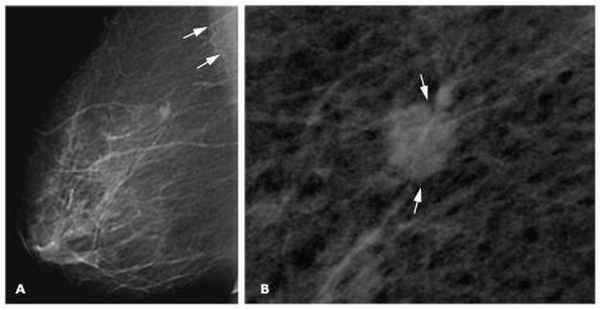

- 3. Двухсторонняя маммография. Изображения, полученные в ходе этого исследования - маммограммы - позволяют оценить внутреннюю структуру молочных желез, а также размер, локализацию и форму опухолевого новообразования.

- Высокая плотность молочной железы, которая выявляется при маммографии.

• маммография (основной метод скрининга)

Ваш врач может выполнять осмотр молочной железы на регулярной основе как часть скрининга. Во время исследования врач внимательно осмотрит и затем ощупает обе молочные железы и подмышечную область. Большинство экспертов рекомендуют проводить осмотр молочных желез, параллельно с маммографией, начиная с 40-50 лет.Маммография

Маммография – рентгеновское исследование молочной железы. Это лучший скрининговый тест для раннего выявления рака молочной железы.![3]()

Диагностика болезни

Наиболее частым симптомом, с которым пациенты обращаются к врачу, является ощущение изменений в молочных железах. Этот симптом является основанием для расширения диагноза за счет проведения других тестов. Важную роль играет врачебный опрос пациентки и, конечно же, визуализирующие исследования в виде маммографии, МРТ и УЗИ. Все должны быть сделаны, поскольку рак может быть замечен только в одном из них.